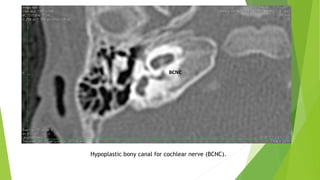

The CA is considered hypoplastic if the width is less than 1.4 mm.

Hypoplastic bony canal for cochlear nerve (BCNC).

Cochlear Aperture Abnormalities TheCA, cochlear fossette, or bony cochlear nerve canal transmits the cochlear nerve from the cochlea to IAC. The CA is considered hypoplastic if the width is less than 1.4 mm.

Hypoplastic bony canalfor cochlear nerve (BCNC).